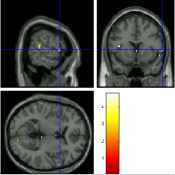

Once the reduced FOV images are available, the proposed pMRI 4D-UWR-SENSE algorithm and its early UWR-SENSE version have been utilized in a final step to reconstruct the full FOV EPI images and compared to the mSENSE Siemens solution. For the wavelet-based regularization, dyadic Symmlet orthonormal wavelet bases [48] associated with filters of length 8 have been used over resolution levels. The reconstructed EPI images then enter in our fMRI study in order to measure the impact of the reconstruction method choice on brain activity detection. Note also that the proposed reconstruction algorithm requires the estimation of the coil sensitivity maps (matrix in Eq. (2)). As proposed in [4], the latter were estimated by dividing the coil-specific images by the module of the Sum Of Squares (SOS) images, which are computed from the specific acquisition of the -space centre (24 lines) before the scans. The same sensitivity map estimation is then used for all the compared methods. Fig. 5 compares the two pMRI reconstruction algorithms to illustrate on axial, coronal and sagittal EPI slices how the mSENSE reconstruction artifacts have been removed using the 4D-UWR-SENSE approach. Reconstructed mSENSE images actually present large artifacts located both at the centre and boundaries of the brain in sensory and cognitive regions (temporal lobes, frontal and motor cortices, …). This results in SNR loss and thus may have a dramatic impact for activation detection in these brain regions. Note that these conclusions are reproducible across subjects although the artifacts may appear on different slices (see red circles in Fig. 5). One can also notice that some residual artifacts still exist in the reconstructed images with our pipeline especially for . Such strong artifacts are only attenuated and not fully removed because of the high level of information loss at .

| mSENSE | 4D-UWR-SENSE | ||

| Axial |  |

|

|

| Coronal | |||

| Sagittal | |||

| Axial |  |

|

|

| Coronal | |||

| Sagittal |